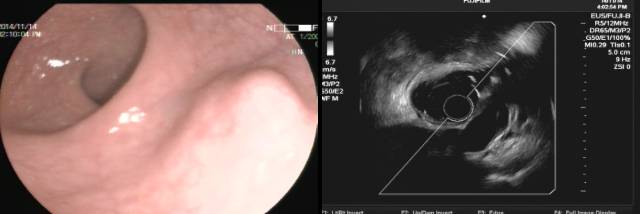

经典EUS教课书上强调用胃壁五层结的完整性来判断外压,但胃底需倒镜探查,EUS扫描平面很难垂直于病灶且信号衰减明显,识别五层结构困难。此时,观察重点应是病灶的内部回声特点,小间质瘤内部为均匀低回声,这和副脾的点状回声完全不同。打个比方,如果让你分辨一只小老虎(间质瘤)和一个家猫(副脾),你可以通过步态和皮毛来判断(相当于观察胃的五层结构),也可以试图掐一下它们,如果发出“瞄”的声音就是家猫(相当于观察病灶内部的回声特点),下面的病例也是通过上述方法诊断为副脾。

该患者也有脾切除病史,胃镜发现胃底隆起,小探头超声见卵圆形病灶,后方膈肌,内部为典型的均匀点状回声,故诊断副脾,从上述两个病例可以看到,如碰到脾切除后的胃底粘膜下隆起,一定要有副脾增生外压的意识。